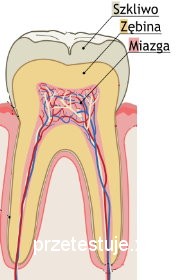

że leczenie kanałowe jest konieczne gdy dochodzi do zmian zapalnych miazgi

zęba tzw. nerwu. Miazgą zęba nazywamy miękką tkankę wypełniającą jamę zęba.

Zawiera ona naczynia krwionośne i tkankę nerwową, które przez otwór w wierzchłku

korzenia przechodzą do kośći.

Miazga pełni przede wszystkim

funkcję odżywczą sieć naczyń krwionośnych zapewnia dostarczanie substancji

odżywczych i tlenu do zęba oraz umożliwia ciągłą kontrolę zawartości substancji

mineralnych. Równie ważną funkcją jest funkcja czuciowa, tj. rejestruje

ból bez względu na rodzaj bodźca i jego lokalizację. Miazga pełni również

funkcję twórczą, gdyż to dzięki jej komórkom zachodzi tworzenie zębiny